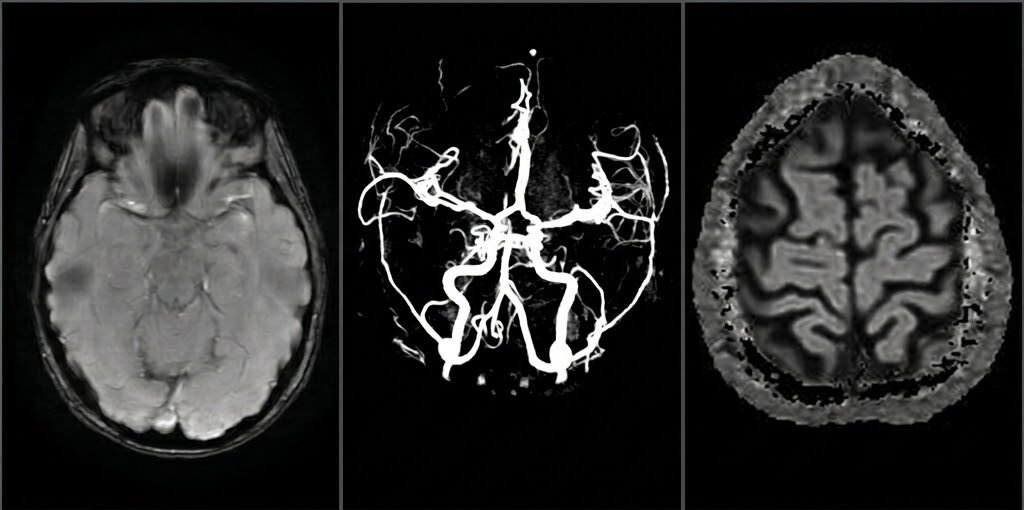

Diario de migrañas (I)